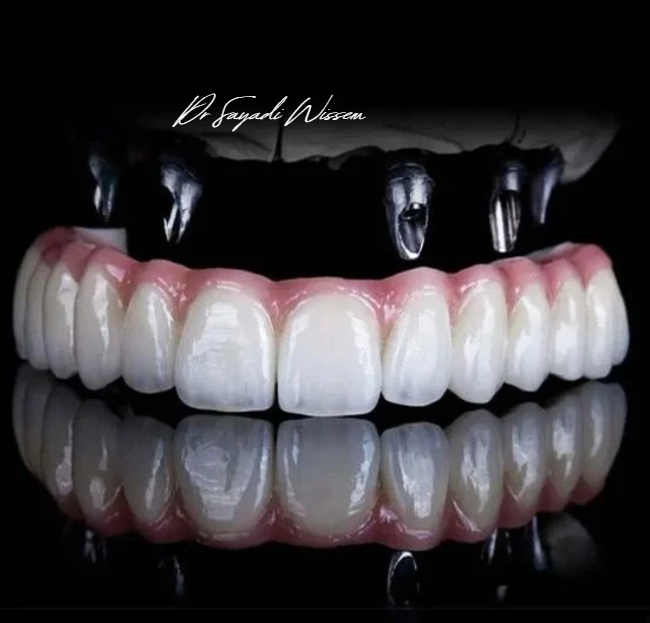

Pack Implant Dentaire

Tout inclus – Qualité garantie